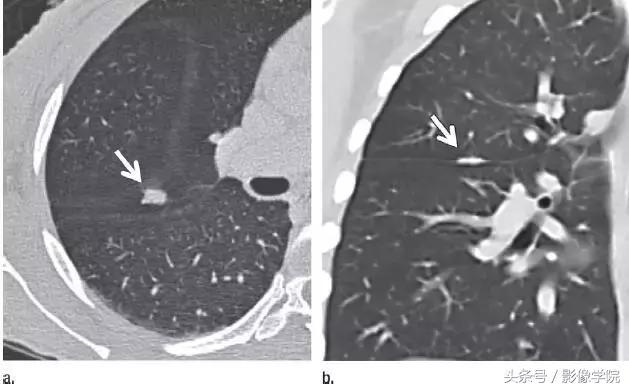

4、良性线状疤痕或淋巴组织

图 4(a)层厚 1 mm 的 CT 横断面图像,显示邻近肺小裂的结节状阴影(箭头)。(b)冠状位重建 CT 图像,显示阴影为良性线状瘢痕或淋巴组织(箭头)。